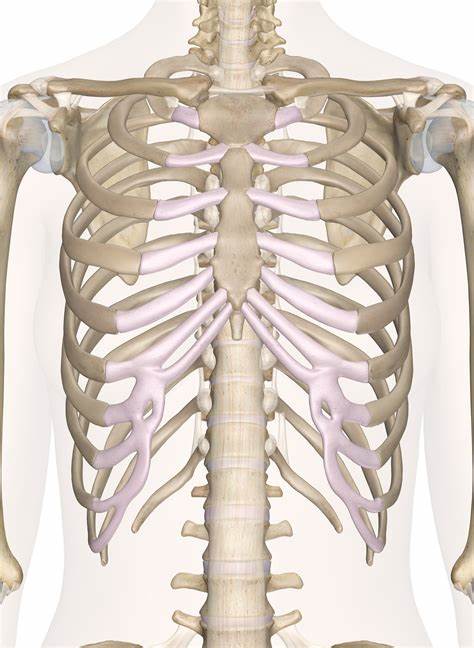

- 了解产后恢复,必须先了解女性骨骼解剖结构,你需要这些信息帮助你理解如何让肚子在最短的时内恢复平坦。我会在这里带你重温一些基础的女性骨骼解剖学内容。妊娠影响最大的骨性结构――骨盆、胸腔和脊柱。盆底由柔软的组织与肌肉构成,它被称为底,因为他处于骨盆的底部,处于耻骨联合与尾椎之间。.....